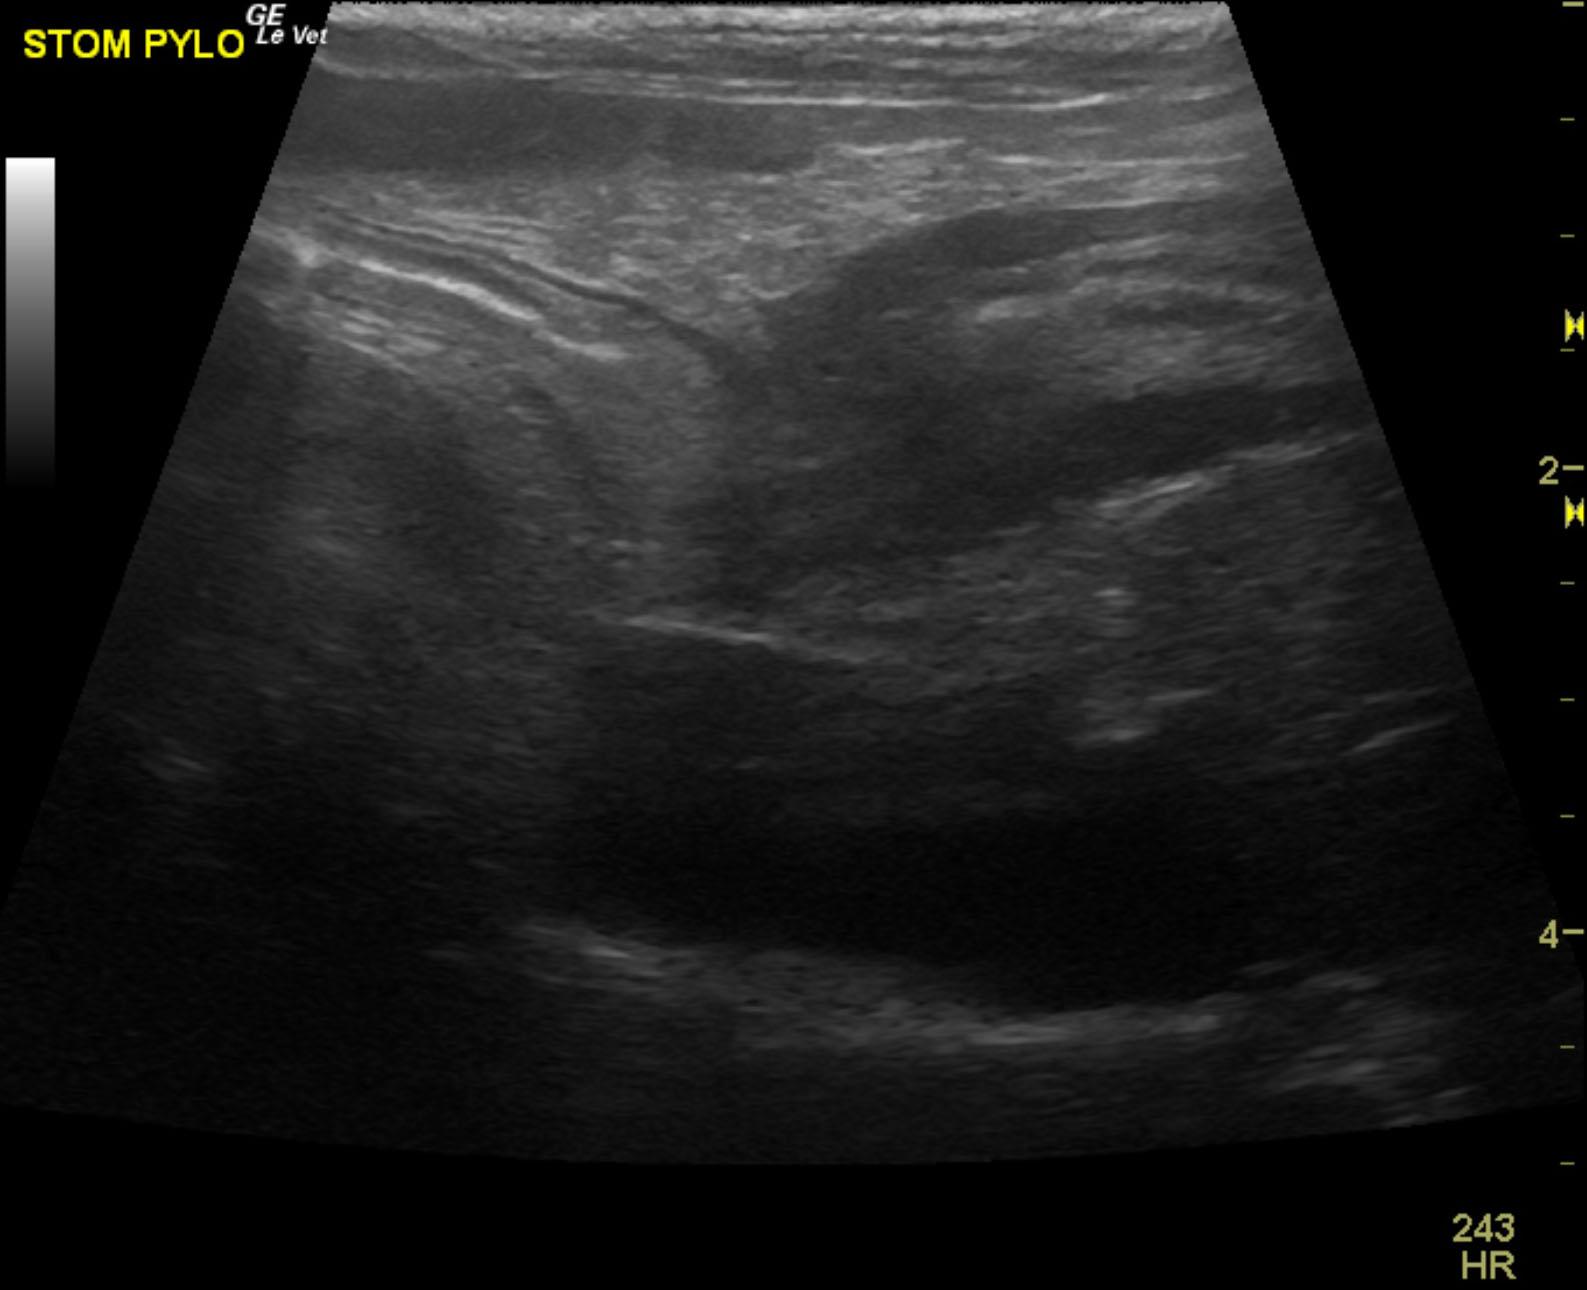

The patient is a 13 year old spayed female Dachshund dog which was presented for four days of anorexia and vomiting. She was given Cerenia, which helped, but still had ileus. Dog has vomited carpet material in past. Spec cPL was normal. Radiographs revealed dilated intestine, which appeared to be colon and cecum.